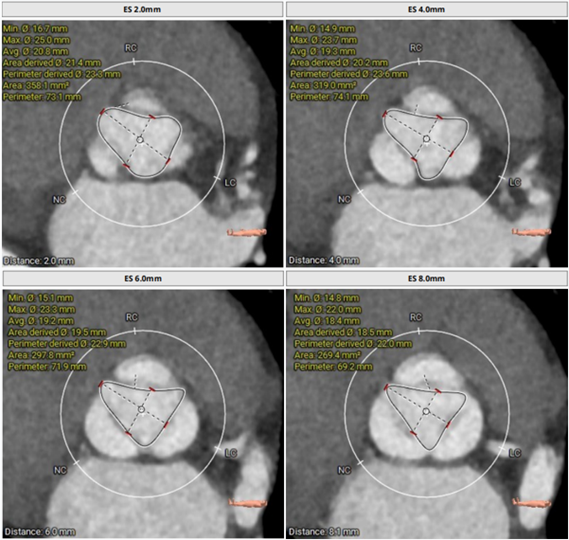

三叶瓣,主动脉瓣瓣环直径23.3mm,瓣环长短径分别为26.5*20.1mm,周长73.2mm,面积为411.9mm²。左室流出道23.7mm,法式窦33.8mm*30.6mm*31.9mm,左冠高度9.1mm,右冠高度15.7mm,窦管交界 35.1mm,升主动脉直径42.5mm。

瓣环直径:23.3mm;周长:73.2mm

根部解剖情况

LCA 高度9.1mm;RCA 高度15.7mm

瓣上多平面测量

术前CT评估

三叶瓣,主动脉瓣环直径22.4mm;瓣环长短径分别为25.2*19.8mm,周长为70.4mm,面积为385.3mm²。左室流出道21.2mm,法式窦28.3mm*28.1mm*28.9mm;

左冠高度11.7mm,右冠高度13.8mm;窦管交界 26.0mm,升主动脉直径33.3mm。

主动脉瓣瓣环直径22.4mm

根部解剖情况

LCA高度 11.7mm;RCA高度13.8mm